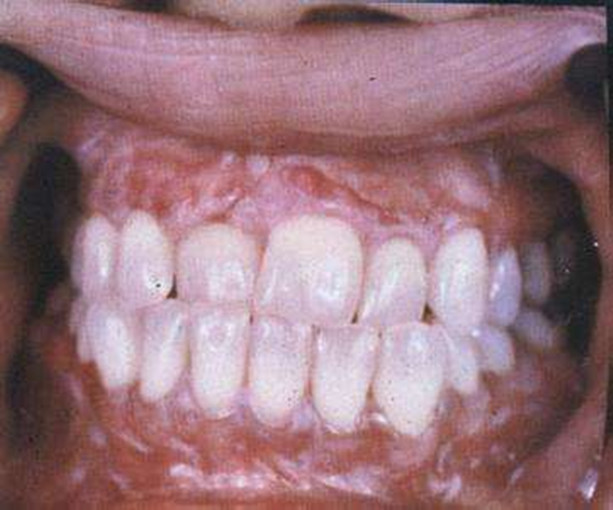

扁平苔癬圖片

牙齦扁平苔蘚

Q:口腔扁平苔蘚症狀表現

A:扁平苔蘚從臨床上很多人沒有症狀,有一些病人會有局部的刺激症狀,比如吃刺激性食物的時候會有一些疼,平時用舌頭舔扁平苔蘚這個部位有一種木的感覺。從外觀上看可以分成網紋型、糜爛型、萎縮型,臨床表現有紅白相間的條紋,還有充血、糜爛,如果是糜爛型吃刺……